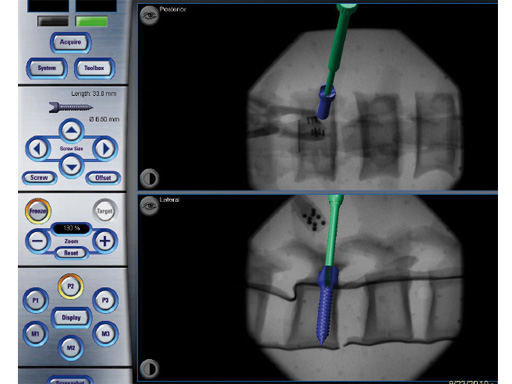

Fig 2 2-D navigation uses image-intensification-based AP and lateral images to track an instruments position in relation to spinal anatomy.

2-D navigation (2-D-nav) uses image-intensification-based AP and lateral images to track an instruments position in relation to the spinal anatomy. It is easier to set up but provides only 2-D information (Fig 2).